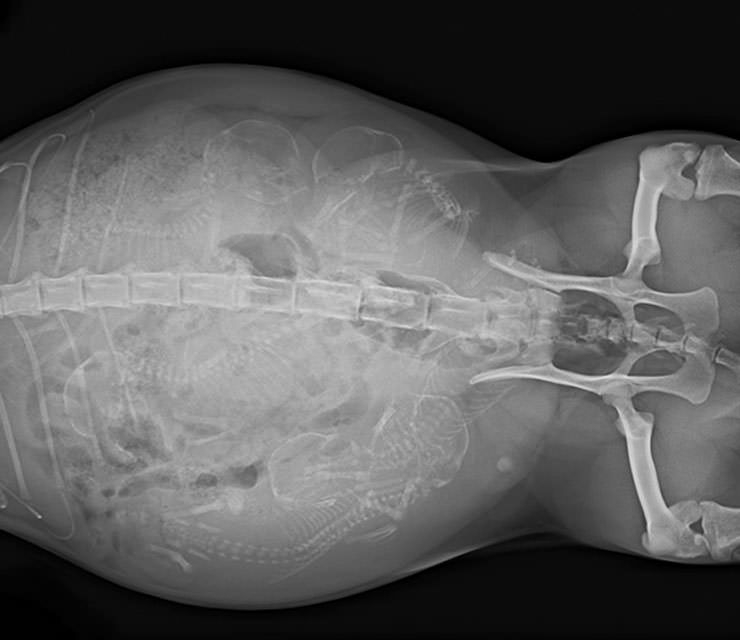

İnsanların ultrason görüntülerini görmeye hepimiz alışkınız. Ancak hamile hayvanların ultrason görüntüleri sizleri çok şaşırtacak.Kaplumbağa

İnsanların ultrason görüntülerini görmeye hepimiz alışkınız. Ancak hamile hayvanların ultrason görüntüleri sizleri çok şaşırtacak.

Kaplumbağa